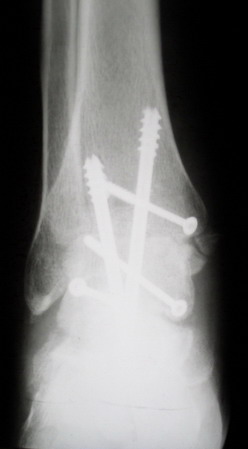

Среди повреждений таранной кости (Hawkins III-IV) с одновременной травмой лодыжек встретилось следующее (см. вложение). Пациент упал в колодец на глубину 10 метров (Х.2002 г.), госпитализирован с диагнозом: з/перелом шейки правой таранной кости (Hawkins IV) с переломовывихом тела назад и кнутри, закрытый перелом внутренней лодыжки и переднего края большеберцовой кости. Оперирован в первые 12 часов после травмы, выполнена открытая репозиция таранной кости, внутренним и передне-внутренними доступами, остеосинтез переломов шейки и тела губчатыми винтами, для реваскуляризации тела таранной кости первичный компрессионный над- и подтаранный артродез. Синтез внутренней лодыжки губчатым винтом. Удаление винтов через 1 год,2 мес. Получен анкилоз указанных суставов с сохранением длины конечности, полная реваскуляризация таранной кости, о чем говорит сращение ее переломов, отсутствие отеков и

цианоза стопы и голени. Компенсаторная подвижность переднего и среднего отделов стопы около 15-20 градусов за счет поперечного (Шопара) сустава стопы. Считаю оправданной подобную тактику, не смотря на угрожаемый прогноз (100% асептический некроз) по классифицкации Hawkins.